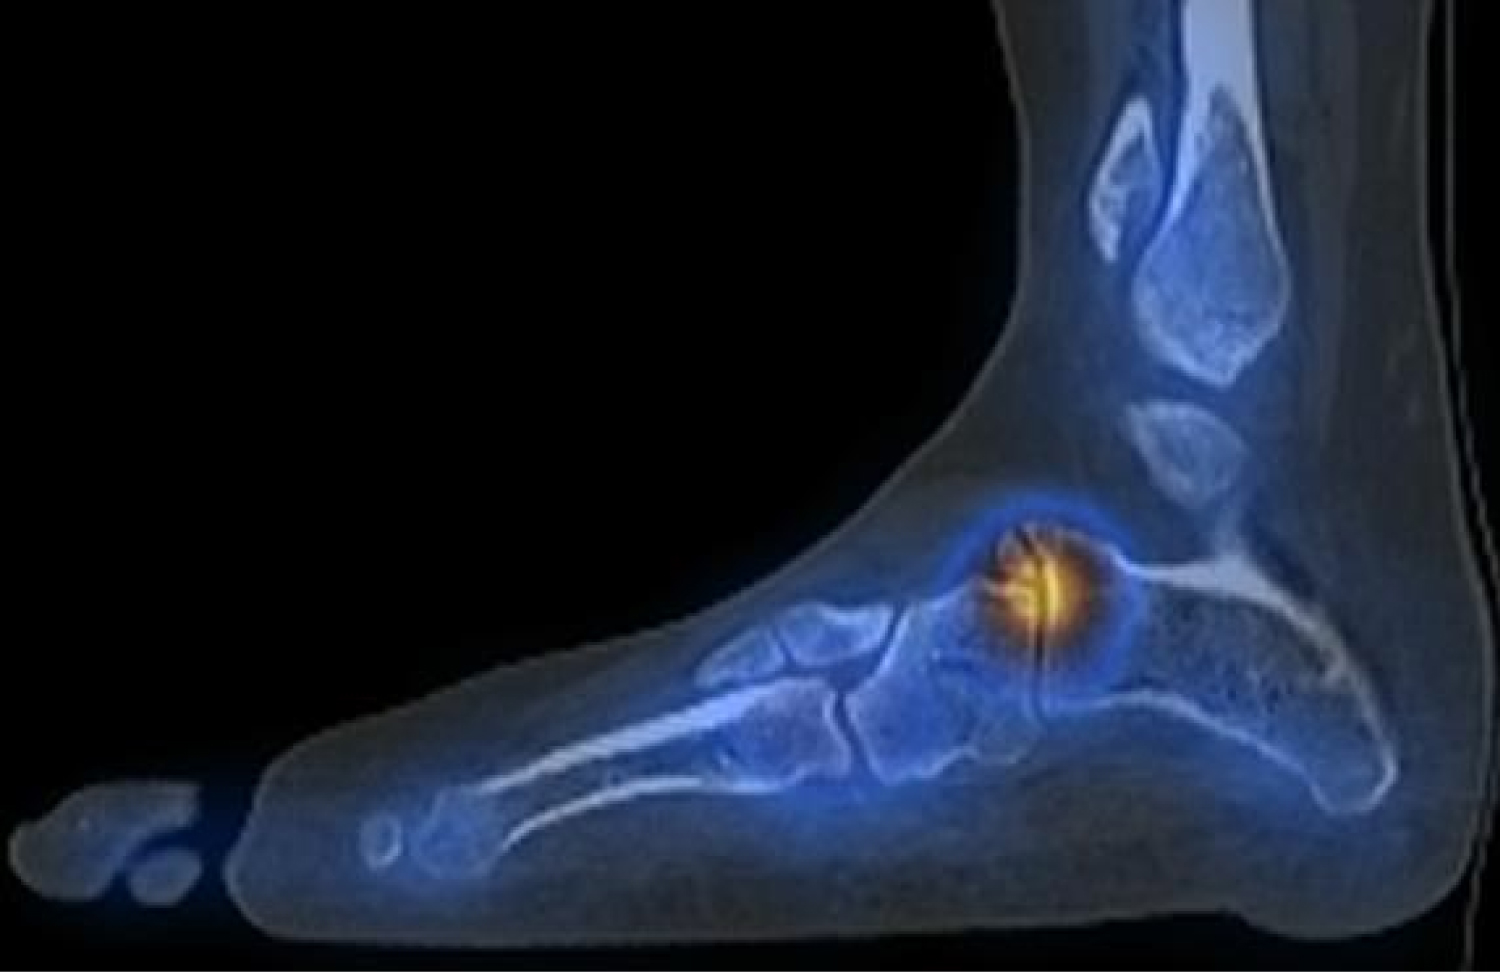

We present the case of a 21-year-old woman with no significant medical history. She was a non-smoker and worked in a supermarket. The patient suffered from an inversion trauma of her left ankle in December 2014. Her clinical symptoms where described as a painful, swollen lateral ankle. She did not tolerate weight bearing during first contact at the emergency department and plain radiographs taken at that time showed no fracture (Figure 1). The patient was diagnosed with a high-grade ankle sprain, the RICE principles where prescribed and the patient was sent home on crutches.

Figure 1: The initial radiographs from the left ankle taken at the emergency department in December 2014: To the left we see a medio-lateral projection and to the right we see the mortise-view into the talo-crural joint. These radiographs were protocoled as normal without posttraumatic injuries. A closer look however to the anterior process of the calcaneus shows a small avulsion. This is easily missed if not specifically looked for. View Figure 1